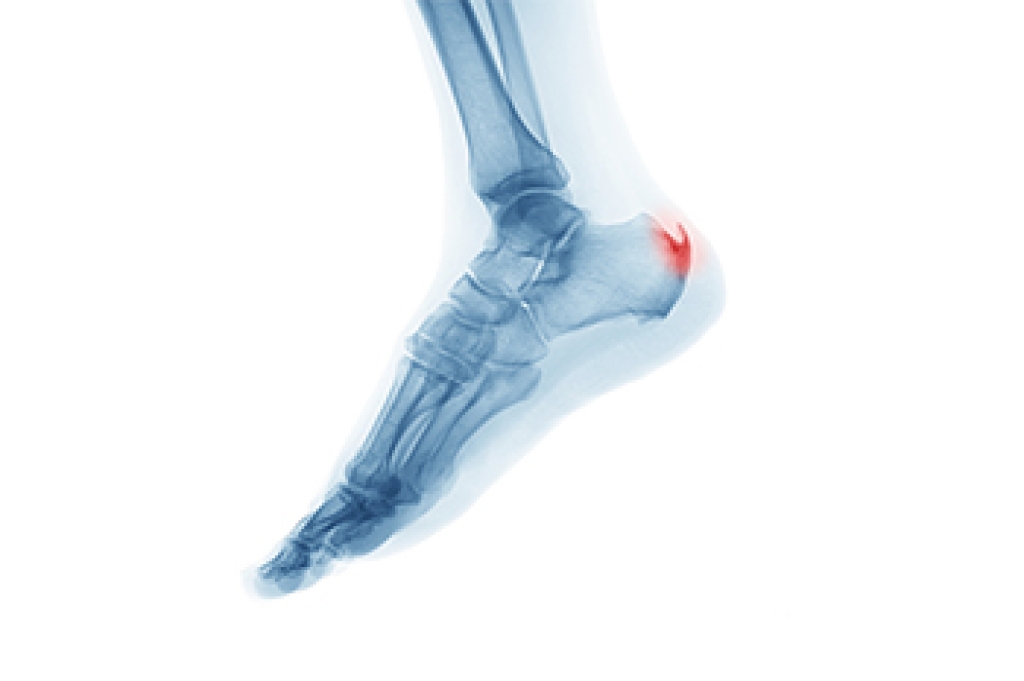

A calcium deposit that forms between the arch of the foot and the heel is referred to as a heel spur. Common symptoms can include heel pain first thing in the morning, followed by a dull ache for the rest of the day. Some patients notice swelling at the front of the heel, and it may feel warm. The heel spur will be visible on an X-ray, and this is a necessary test to have in determining what the proper treatment is. Heel spurs can develop as a result of the aging process when the soft tissue wears thin. People who frequently run may experience this condition, as the heel pad loses shock absorption. Relief may come from elevating the affected foot as often as possible, and this can help to reduce swelling. Additionally, wearing shoes that have a cushion may help to ease the pain that can come from having a heel spur. Many patients who have heel spurs find it is difficult to complete daily activities. If this applies to you or someone you know, it is strongly suggested that you consult with a podiatrist.

Heel spurs are formed by calcium deposits on the back of the foot where the heel is. This can also be caused by small fragments of bone breaking off one section of the foot, attaching onto the back of the foot. Heel spurs can also be bone growth on the back of the foot and may grow in the direction of the arch of the foot.